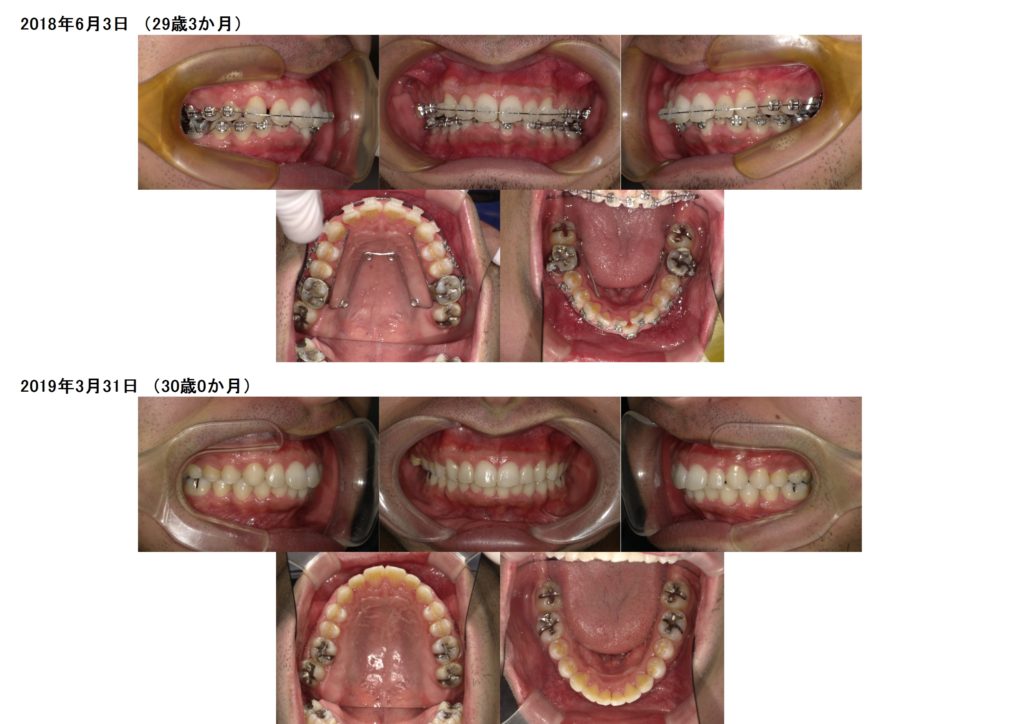

男性の方でもこのようにブラケット治療をされますよ☆

思っていたより、気づかれなかった。そんなに目立たないですね。と言われる方も多いですよ。

とってもキレイになりましたよね!!